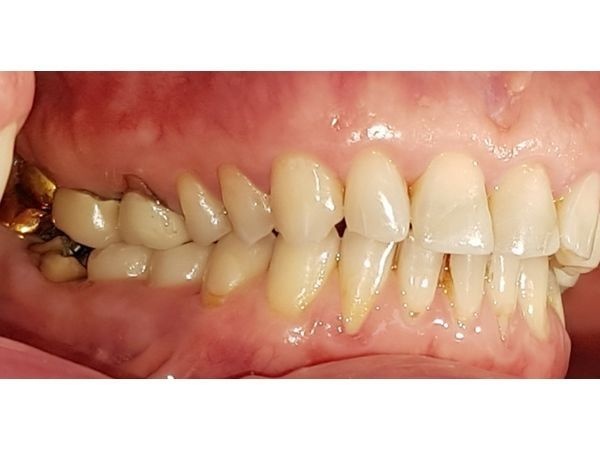

Импланты и коронки на нижние моляры (зубы 35, 36, 45 и 46) установили около 2 лет назад в другой клинике. Примерно через год слизистая вокруг них воспалилась и отекла. Ещё спустя полгода женщина отметила разрушение жевательных зубов 37 и 47.

Металлические штампованные коронки также стоят на 18, 28 и 38-м моляре.

КТ показала очаги повреждения костной ткани вокруг имплантов, неточность прилегания коронок и большую зону разрушения кости в области 47-го зуба.

Пациентке сняли все коронки с зубов и имплантов. На зубы, которые можно было сохранить, изготовили временные коронки, остальные зубы, поражённые периодонтитом, и импланты удалили. На их месте провели костную пластику и имплантацию.